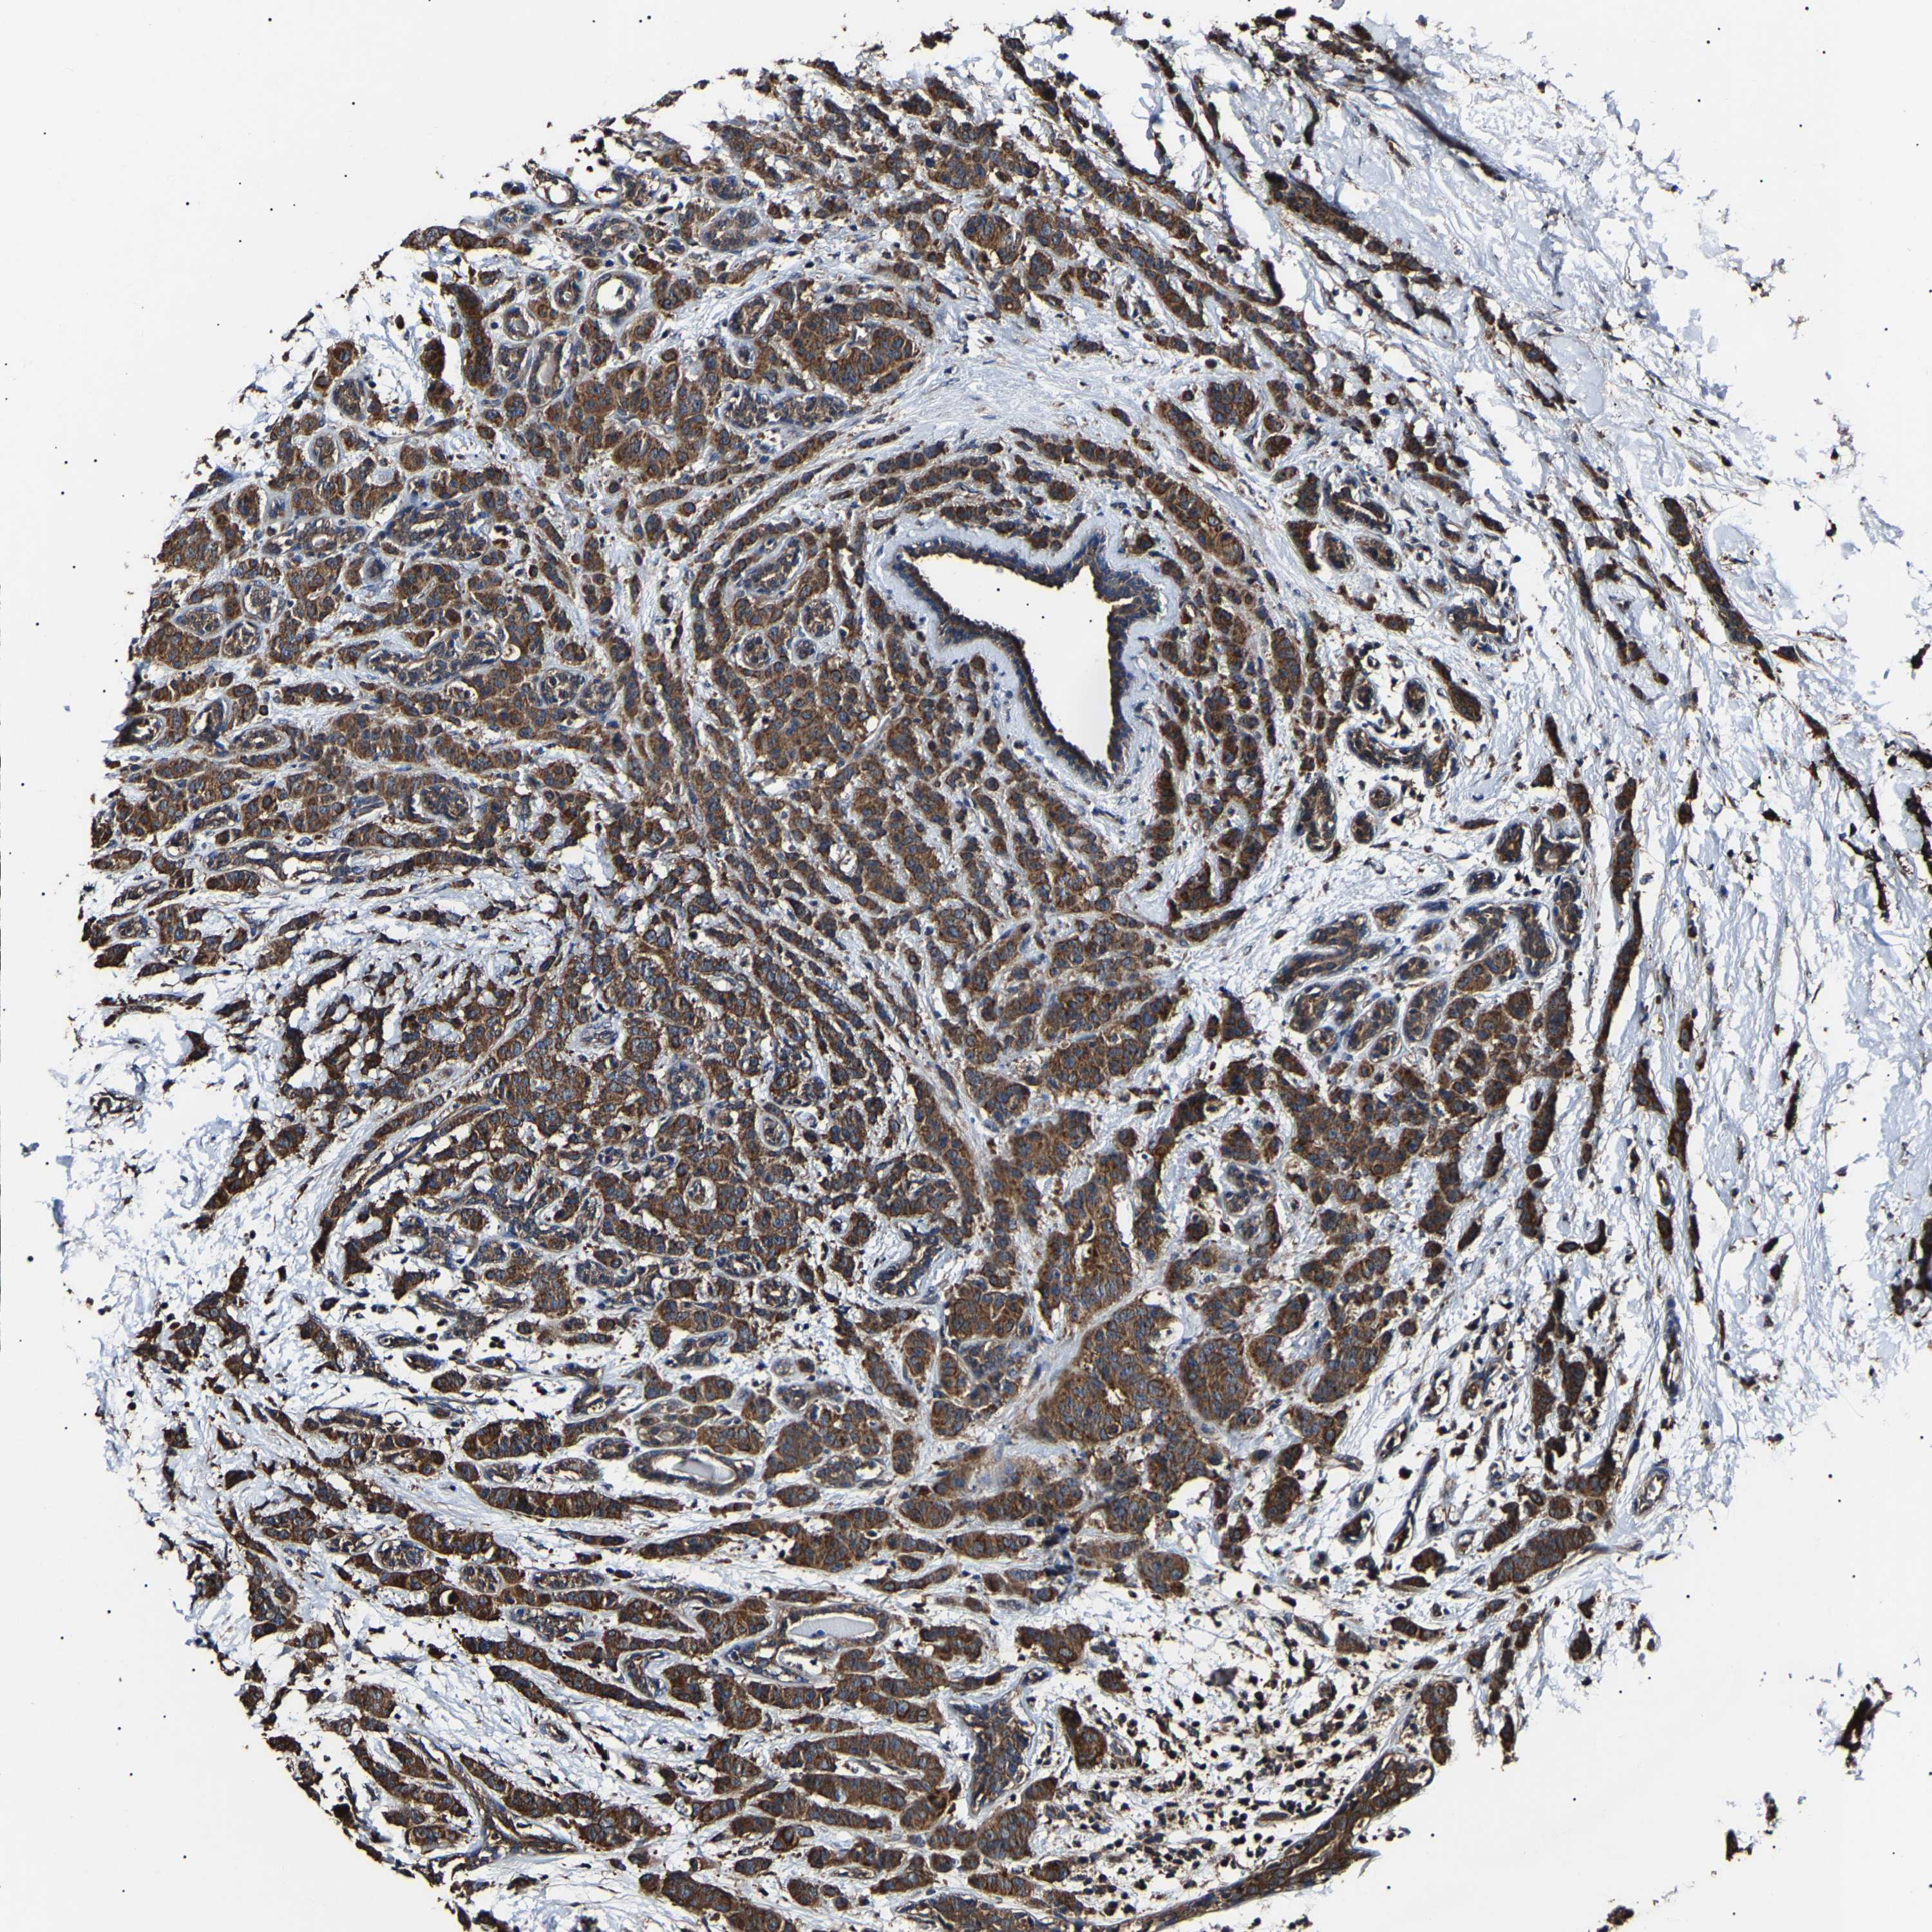

CANCER BREAST CANCER Show tissue menu

Breast cancer

Human cancer